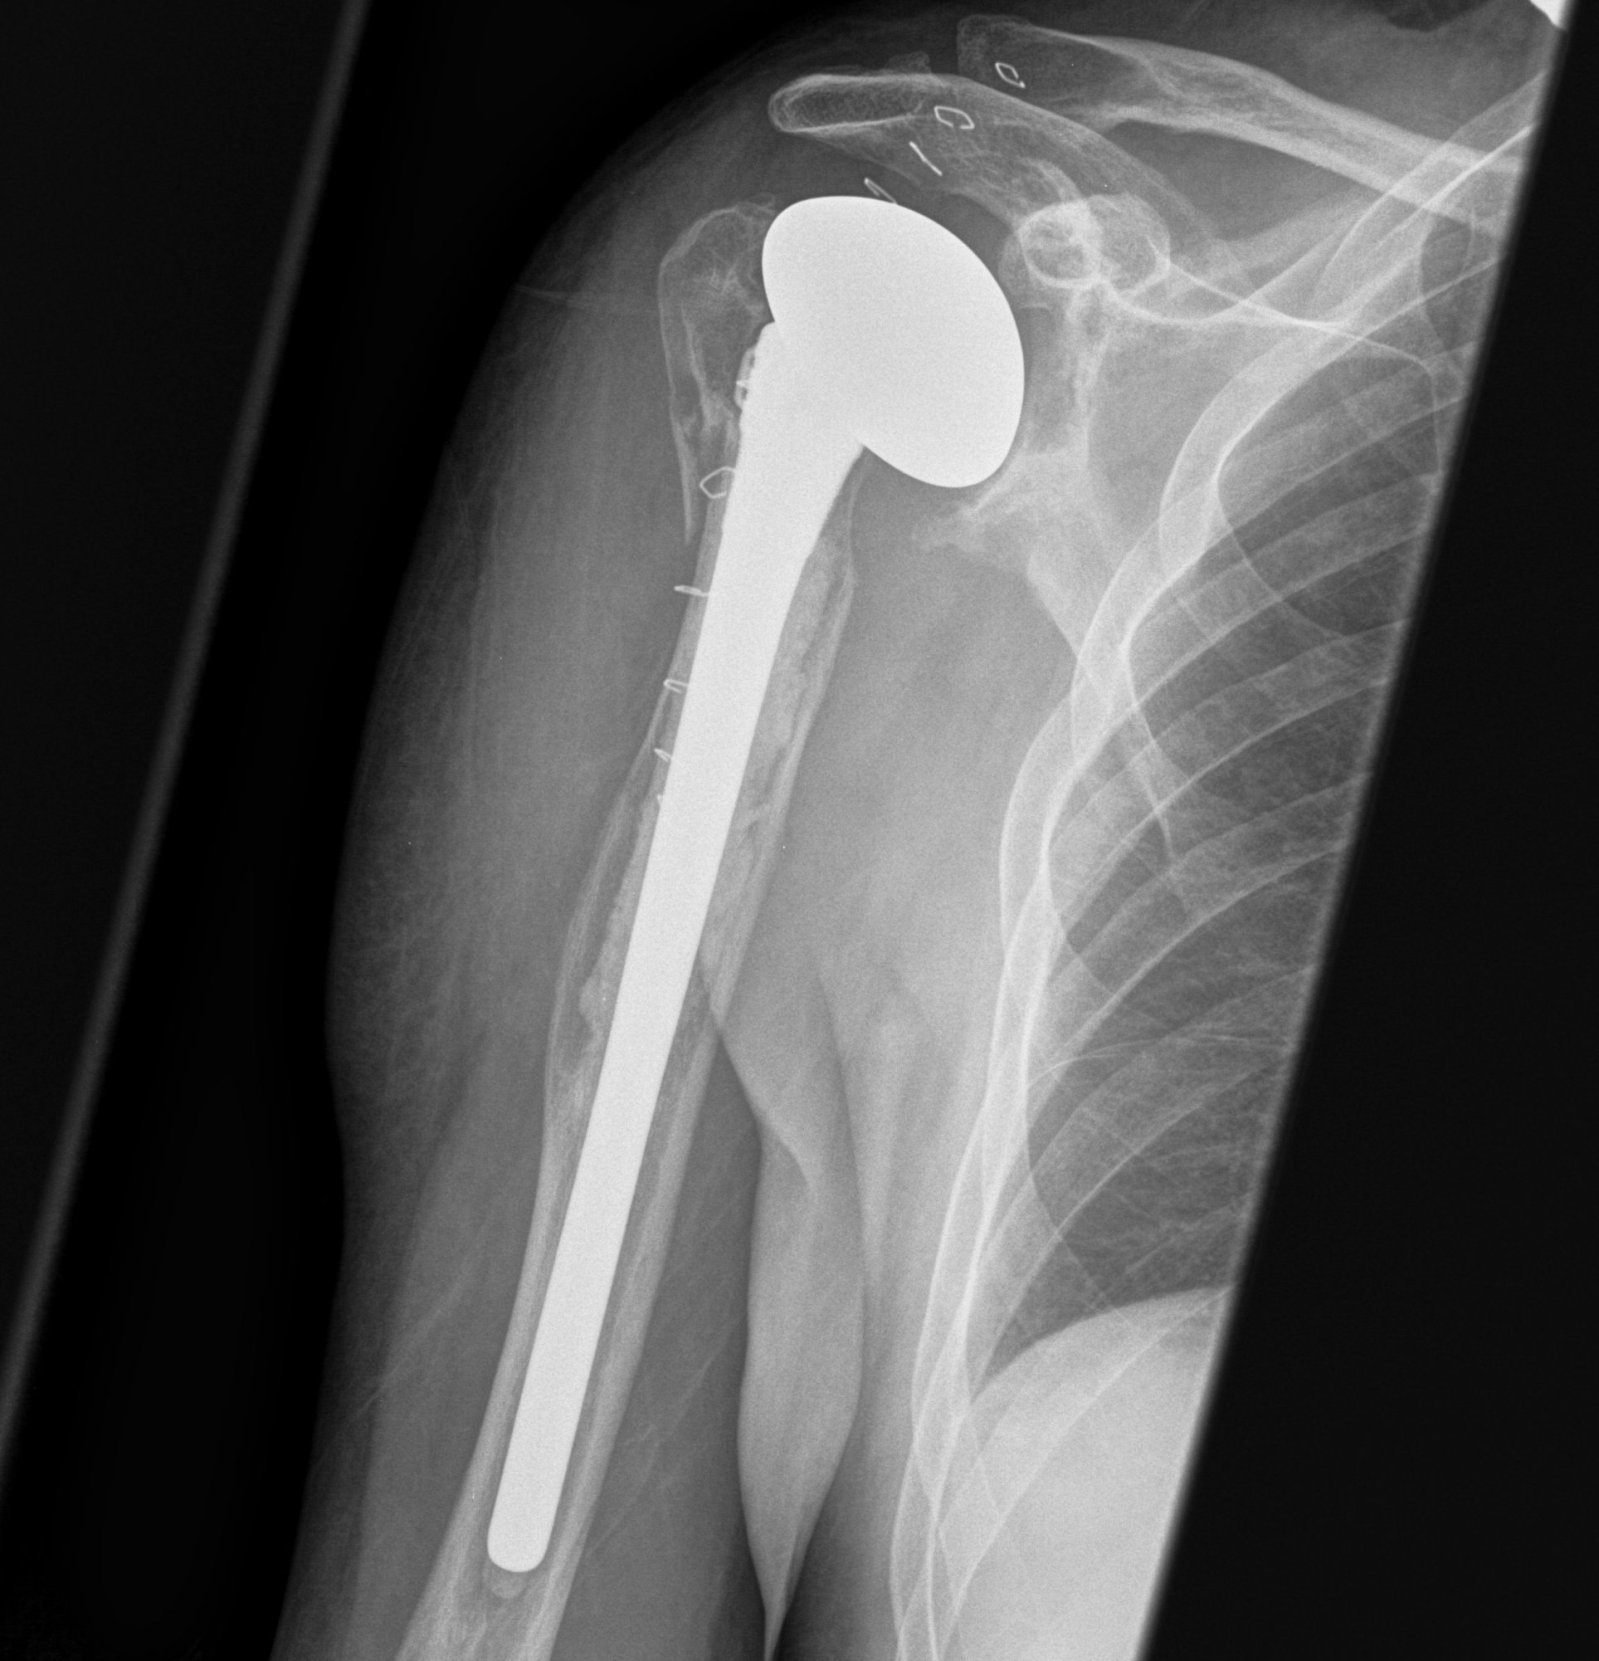

May need proximal humerus allograft

Sanchez - Sotelo et al. JBJS Am 2017

- 26 patients undergoing revision to reverse with bulk proximal allograft

- average time to union 7 months

- one patient required bone grafting to obtain union